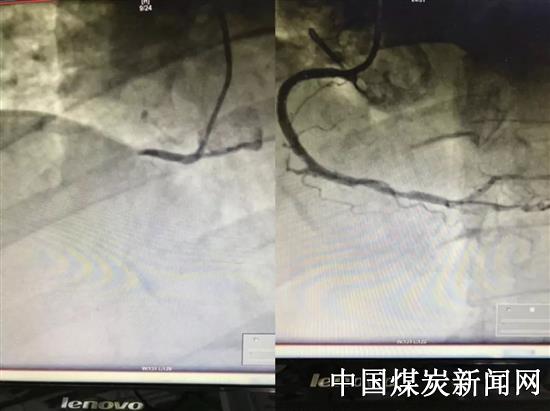

原来,前不久孙师傅因胃痛被送到内二科,他表情痛苦,面色惨白,四肢厥冷,周身乏力,瘫软在床。内二科主任孟利敏诊断为急性下壁心肌梗死,患者发病时间2小时,无明显禁忌症,为挽救濒死心肌,抢救患者生命,孟主任建议患者立即行冠脉造影术及必要时支架植入术,开通闭塞血管,改善患者愈后。一小时后,手术顺利完成。医护人员与时间赛跑,与死神争夺,最终将孙师傅抢救回来!